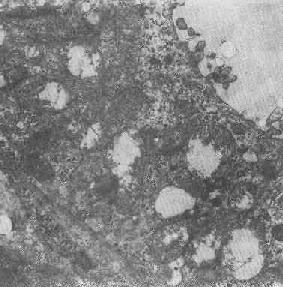

图1-9 线粒体肿

四、线粒体线粒体(mitochondrion)是细胞内主要的能量形成所在,故不论在生理上或病理上都具有十分重要的意义。 线粒体为线状、长杆状、卵圆形或圆形小体,外被双层界膜。外界膜平滑,内界膜则折成长短不等的嵴并附有基粒。内外界膜之间为线粒体的外室,与嵴内隙相连,内界膜内侧为内室(基质室)(图1-8)。在合成甾类激素的内分泌细胞(如肾上腺皮质细胞、卵甾滤泡细胞、睾丸的Leydig细胞等),线粒体嵴呈小管状。内外界膜的通透性不同,外界膜的通透性高,可容许多种物质通过,而内界膜则构成明显的通透屏障,使一些物质如蔗糖和NADH全然不能通过,而其他物质如Na+ 和Ca 2+等也只有借助于主动运输才能通过。线粒体的基质含有电子致密的无结构颗粒(基质颗粒),与二价阳离子如Ca2+及Mg2+具有高度亲和力。基质中进行着β氧化、氧化脱羧、枸橼酸循环以及尿素循环等过程。在线粒体的外界膜内含有单胺氧化酶以及糖和脂质代谢的各种转移酶;在内界膜上则为呼吸链和氧化磷酸化的酶类。 线粒体是对各种损伤最为敏感的细胞器之一。在细胞损伤时最常见的病理改变可概括为线粒体数量、大小和结构的改变: 1.数量的改变 线粒体的平均寿命约为10天。衰亡的线粒体可通过保留的线粒体直接分裂为二予以补充。在病理状态下,线粒体的增生实际上是对慢性非特异性细胞损伤的适应性反应或细胞功能升高的表现。例如心瓣膜病时的心肌线粒体、周围血液循环障碍伴间歇性跛行时的骨骼肌线粒体的呈增生现象。 线粒体数量减少则见于急性细胞损伤时线粒体崩解或自溶的情况下,持续约15分钟。慢性损伤时由于线粒体逐渐增生,故一般不见线粒体减少(甚至反而增多)。此外,线粒体的减少也是细胞未成熟和(或)去分化的表现。 2.大小改变 细胞损伤时最常见的改变为线粒体肿大。根据线粒体的受累部位可分为基质型肿胀和嵴型肿胀二种类型,而以前者为常见。基质型肿胀时线粒体变大变圆,基质变浅、嵴变短变少甚至消失(图1-9)。在极度肿胀时,线粒体可转化为小空泡状结构(图1-10,图1-11)。此型肿胀为细胞水肿的部分改变。光学显微镜下所谓的浊肿细胞中所见的细颗粒即肿大的线粒体。嵴型肿较少见,此时的肿胀局限于嵴内隙,使扁平的嵴变成烧瓶状乃至空泡状,而基质则更显得致密。嵴型肿胀一般为可复性,但当膜的损伤加重时,可经过混合型而过渡为基质型。 线粒体为对损伤极为敏感的细胞器,其肿胀可由多种损伤因子引起,其中最常见的为缺氧;此外,微生物毒素、各种毒物、射线以及渗透压改变等亦可引起。但轻度肿大有时可能为其功能升高的表现,较明显的肿胀则恒为细胞受损的表现。但只要损伤不过重、损伤因子的作用不过长,肿胀仍可恢复。 线粒体的增大有时是器官功能负荷增加引起的适应性肥大,此时线粒体的数量也常增多,例如见于器官肥大时。反之,器官萎缩时,线粒体则缩小、变少。